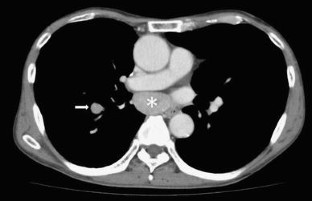

Hepatocellular carcinoma occasionally metastasizes to extrahepatic organs, rarely to the mediastinal lymph nodes. We present the case of a 64-year-old man who presented with nodules in the upper and right lower lobes of the lung 4 years after undergoing resection of a hepatocellular carcinoma. We performed wedge resection of both lesions. Pathological examination showed that the lesion in the right upper lobe was non-small cell lung cancer and that in the right lower lobe hepatocellular carcinoma. We accordingly performed right upper lobectomy with lymph node dissection. Nine months later, enlarged subcarinal and segmental lymph nodes were detected and mediastinal lymph node metastases from the hepatocellular carcinoma diagnosed by transbronchial needle aspiration.

Fig. 1

Fig. 2

Fig. 3